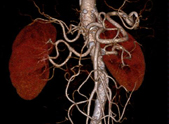

• Gefäße

CT-Angiographie ist ein spezielles Röntgen-Schnittbildverfahren zur Untersuchung und sehr exakten Lokalisierung von aterosklerotischen Veränderungen an Herz und Gefäßen.

Die CT-Angiographie (auch CTA) erlaubt die kontrastmittelverstärkte Darstellung von Gefäßen in allen Körperregionen, ohne dass ein arterielles Gefäß punktiert werden muss.

Durch die gleichzeitige Erfassung von Gefäßwand, Lumen und der Umgebung erhält man informationsdichte Bilder, die mit geeigneten Softwareverfahren zur Visualisierung (z.B. MPR, MIP und VRT) zur zwei- und dreidimensionalen Gefäßdiagnostik eingesetzt werden.

Mit unserem 256-Schichten-FLASH-CT lassen sich im Spiralmodus auch lange Gefäßstrecken, etwa in Bauch- oder Bein-Becken-Bereich in einem einzigen Untersuchungsgang erfassen.